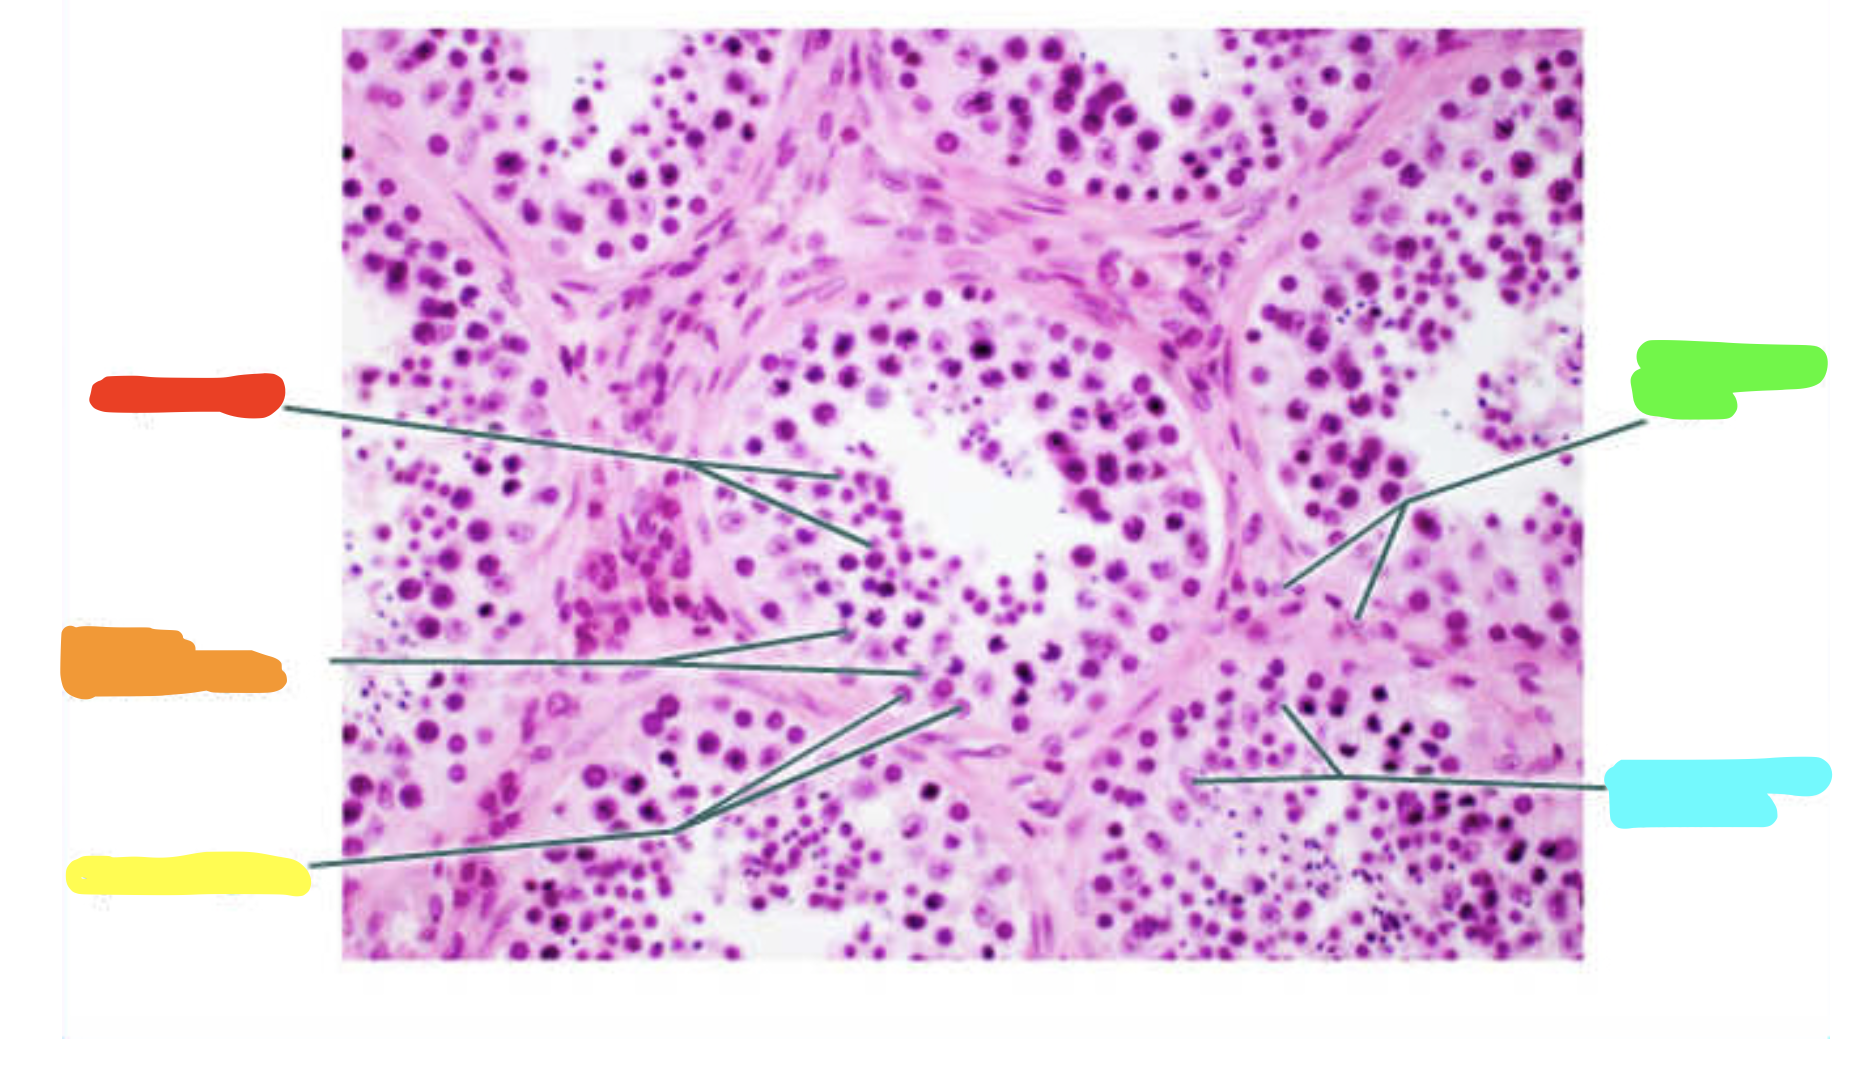

What is this a slide of?

Testis

What is red?

Primary spermatocytes

What is orange?

Spermatogonia

What is yellow?

Spermatids

What is green?

Sustentacular cell nuclei